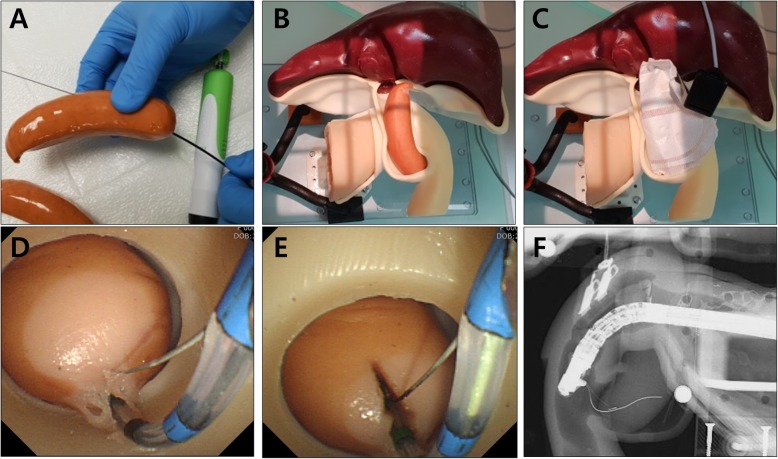

Digital 3D models of stomach and duodenum were obtained by importing the CT image data to the in-house software by StereoLithography (STL) file format. In addition, a hepatobiliary system, consisting of the ampulla of Vater, pancreatic duct with pancreas, common bile duct (CBD), gallbladder, liver, and intrahepatic bile ducts, was implemented in three dimensions using two open source programs of MeshLab and MeshMixer (Fig. 1a). In this study, endoscopic training in various anatomy of the ampulla of Vater and CBD had to be emphasized. Therefore, removable ampullary and CBD modules were mounted on the base of phantom (Fig. 1b and c). For performing different therapeutic procedures, eight different types of ampullary and CBD modules were separately designed to be utilized and repeatedly replaced on the base of phantom (Figs. 2 and 3).

The main parts produced in this phantom were the lower stomach and duodenum, the ampullary and CBD module, the liver having intra hepatic bile ducts, and finally the saddle that can stably support them. In this study, all organ parts were fabricated using silicone molding techniques with 3D printing, while only the saddle part was produced directly by the 3D printer (3DM Tough-3.6, 3DMaterials, Zeron-2500, Zeron, Korea). In order to manufacture each of the designed organ parts with silicone, a negative part had to be newly designed to produce the molder. The negative molders were 3D printed (3DM DW-06, 3DMaterials, Zeron-2500, Zeron, Korea) and then injection molding was applied to obtain organ parts in silicone material (Dragon Skin 10, Smooth-on, USA; shore A (hardness) = 10, elongation = 1000%).

Position and orientation of the ERCP phantom

For ERCP training, it is important to acquire real-time fluoroscopic images as well as endoscopic images. We fixed the ERCP phantom with a supporting stand, also made by the 3D printing technique, in the prone position as in a common ERCP procedure position (Fig. 1b). Because the shortening step was omitted during duodenoscope insertion into the area of ampulla, and the phantom was inversely located on the fluoroscopy table, it was necessary to adjust the direction of the fluoroscopic imaging (Fig. 4). It was not necessary to adjust the direction of endoscopic imaging.

Endoscopic sphincterotomy was performed on a specialized ampulla using a Vienna sausage (Fig. 8). Before the assembly of the sausage into the module area of the phantom, a small tract was made in the sausage using an endoscopic ultrasound-guided biopsy needle (Acquire™ needle, Boston Scientific Co.). The electrical plate (Erbe Nessy® Omega Plate, Erbe Elektromedizin GmbH, Tübingen, Germany) was attached to the sausage for electric current flow. After the insertion of a guidewire and sphincterotome (Tri-Tome PC Protector, Cook Medical Inc., Winston-Salem, NC) into the small tract of the sausage, endoscopic sphincterotomy was successfully performed using an electrosurgical unit (VIO 300D, Erbe Elektromedizin GmbH; Endo cut mode, effect 3, cut duration 2, cut interval 3) (Video 1 shows the implementation of all ERCP procedures using the ERCP phantom).

In order to make the experience of being placed around the duodenal ampulla and the feeling of using various ERCP accessories as realistic as possible, 3D modeling data were obtained from human CT images, as per previous reported studies [ref. 13–ref. 15]. One of important steps in this process was to make the stomach and duodenum. We wanted to make a model where the duodenoscope could be inserted in a sequence that followed from esophagus, stomach, and duodenum, but since silicone material was not elastic and stretchable like the human stomach, we decided to cut the stomach for easy insertion of duodenoscope around the duodenal ampulla and omitted the shortening step. Therefore, insertion of the duodenoscope was not difficult, but the direction of the fluoroscopic image had to be inevitably adjusted because of the difference in direction as compared to an actual human (Fig. 5). Another important step in the designing process was to make the ampulla and CBD in various shapes. If this part could be made into various shapes, it could be implemented for various training models and disease models. In order to resolve this issue, we implemented a new 3D printing method to make these parts in various forms, and to connect them to the main body in a module-type assembly format. Another important step was to implement the sphincterotomy model. For the new model to be appealing and used widely in future, it was necessary that it should be more convenient, cost-effective, and reusable than the previous models. As mentioned for other modules, it had to be easily assembled with the main body, electrically operated, easy to store, and relatively inexpensive. Because the present silicone-material phantom utilizes injection molding technique, it can secure many economic benefits in re-production. Since re-production requires only silicone materials and injection molding efforts, we can save the cost of designing for positive phantom model and negative molder model, and the cost of 3D printing of negative molder as well. Therefore, it is possible to reproduce the same phantom at a price of one-third. Because the present phantom has modular configuration, in addition, it can be implemented with minimal efforts of designing and 3D printing for additional variant designs. While looking for suitable material, the curved Vienna sausage met all the conditions for eligibility and could be used in variable sizes and shapes. Also, it is very similar to the practice in the human body, and creating the sphincterotomy model was a very positive and reaffirming experience.